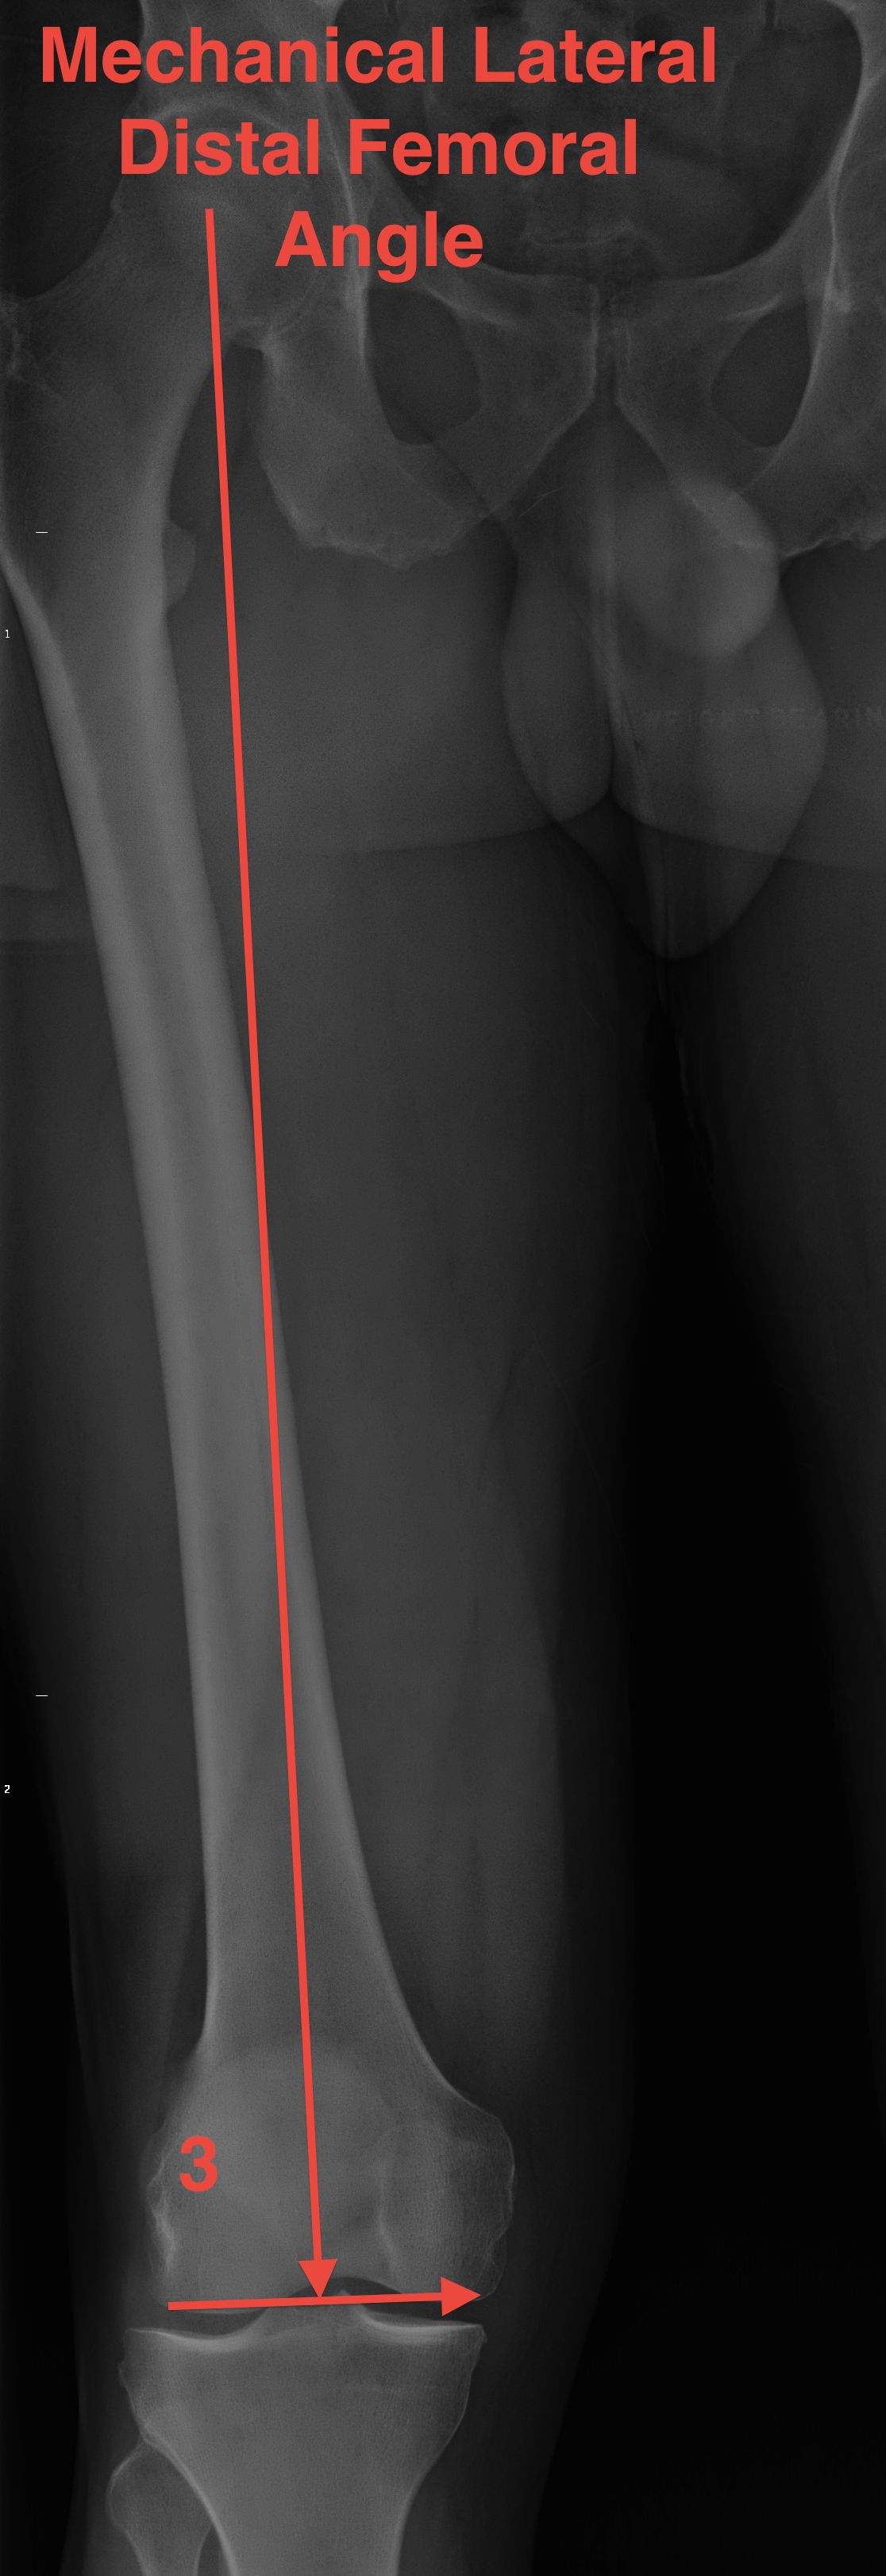

mLDFA (mechanical Lateral Distal Femoral Angle) |

| 3o valgus relative to MA | 81o | 87o | 87o or 3o varus | 9° |

| 6o valgus distal femur | ||||